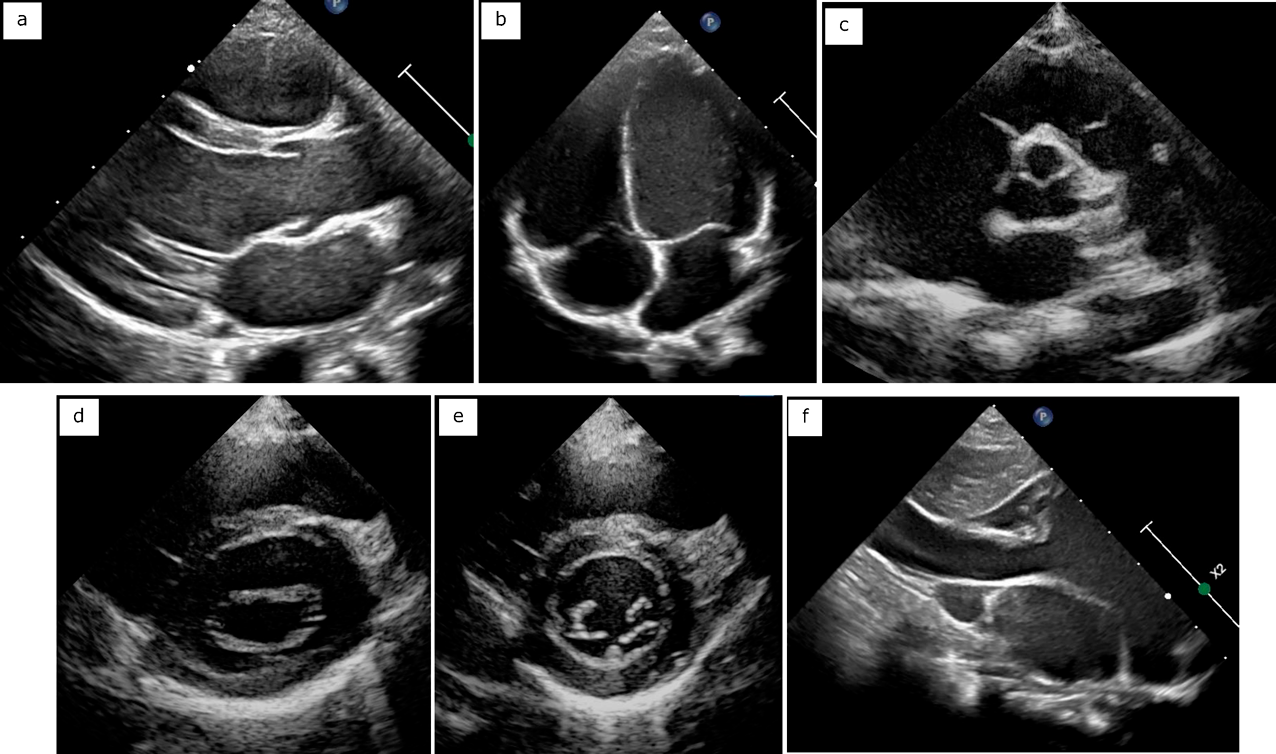

それぞれの弁輪と血管の計測を示す(Figs. 5, 6).いずれも最大となる時相で内膜面間の距離(trailing edge to leading edge)を計測する.僧帽弁輪径,三尖弁輪径は心尖部四腔断面と傍胸骨長軸断面でそれぞれ計測する.最大径となる拡張期で弁付着部を計測することが一般的であり,楕円形の房室弁輪形態を反映してそれぞれの計測部位で正常値が異なる.大動脈弁輪径は傍胸骨長軸断面で計測し,最大径となる収縮期で計測する.同様にバルサルバ洞径,接合部径,上行大動脈径も計測するが,これらの部位は成人ガイドラインにおいて拡張末期にleading edge to leading edgeでの計測が推奨されており,施設内での統一が望ましい.肺動脈弁輪径は収縮期の傍胸骨短軸断面で計測し,主肺動脈径,左右肺動脈径の計測も行う.症例によっては傍胸骨長軸断面のほうが描出しやすいことがある.大動脈弓は胸骨上窩断面から体位の工夫を併用して描出し,近位(無名動脈–左総頚動脈間),遠位(左総頚動脈–左鎖骨下動脈間),峡部(左鎖骨下動脈以遠の最狭部)を計測する.下大静脈は心窩部断面で下行大動脈との位置関係と流入する心房を確認し,右房に連続する断面で計測するとともに呼吸による変動を観察する.肺静脈は心尖部断面と胸骨上窩断面で左房への流入を確認する.冠動脈は傍胸骨短軸断面の大動脈弁レベルから左右冠動脈起始部を描出し,流速を下げたカラードプラを併用する.

Pediatric Cardiology and Cardiac Surgery 41(1): 20-27 (2025)

Fig. 6 Measurements of vessels

a. Mein, right and left pulmonary artery. b. Valsalva, ST junction, ascending aorta. c. Arch. d. Pulmonary veins. e. Inferior vena cava. f. Coronary artery. Asc Ao, ascending aorta; IVC, inferior vena cava; LA, left atrium; LCA, left coronary artery; LLPV, left lower pulmonary vein; LPA, left pulmonary artery; LUPV, left upper pulmonary vein; MPA, main pulmonary artery; RCA, right coronary artery; RLPV, right lower pulmonary vein; RPA, right pulmonary artery; RUPV, right upper pulmonary vein; STJ, sinotublar junction.